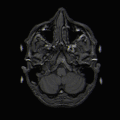

After concluding that syntax and semantics were separate from one another, Friederici et al (2003) used functional magnetic resonance imaging (fMRI) to try and localize the areas involved. fMRI analysis localized the N400 ERP from semantic processing within the brain: the hippocampus may be involved, cortical areas within the superior temporal sulcus, and the left auditory cortex. When using fMRI to analyze the ELAN involved in syntactic processing it was found that the ELAN was localized within the anterior temporal and inferior frontal cortices in both hemispheres, but there was left hemisphere dominance. Friederici et al (2003) designed an experiment using anomalous sentences (abnormal sentences) in order to localize the regions involved in the P600. Friederici et al's (2003) study did identify that the left basal ganglia of the putamen was associated with the P600 potential. It was found to be involved in the later controlled syntactic processing rather than with the early structure building processes. This study did show that there was a difference between semantic and syntactic processing, as well showed the different regions within the brain associated with the two ERPs involved in syntactic processing. Latter studies found that in patients who had neuro-debilitating diseases like Parkinson's disease had a reduced P600 potential as a result of impaired basal ganglia.

fMRI scan of WikiCommonUser:Fastfission user's brain